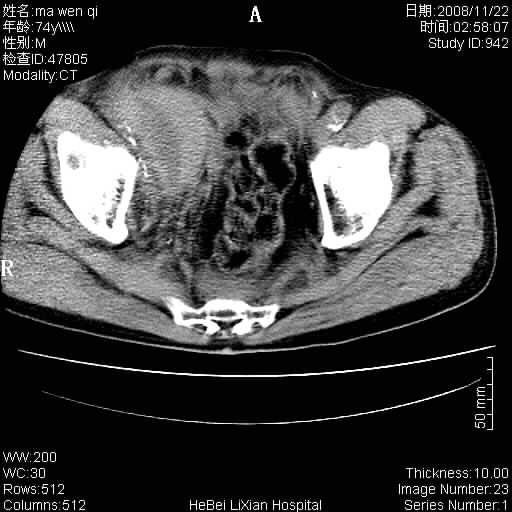

患者男 74岁.突然昏迷,休克6小时.血压70/30,头颅ct未见异常,既往体健.

补充病史,保留导尿10小时,尿袋内只有少许尿液,患者于住院后15小时后去世.

腹主动脉、双侧髂动脉夹层动脉瘤破裂出血进入腹腔。

考虑双侧髂a瘤,伴破裂出血

腹主动脉、双侧髂动脉夹层或动脉瘤破裂出血进入腹腔

1)考虑双侧髂动脉瘤并右侧动脉瘤破裂出血,右侧腹膜后及腹腔积血。2)双侧腹股沟疝。

支持(1)双侧髂动脉瘤并右侧动脉瘤破裂出血,右侧腹膜后及腹腔积血。(2)双侧腹股沟疝。

1)考虑,腹主动脉、双侧髂动脉夹层动脉瘤破裂伴右侧腹膜后及腹腔积血。2)双侧腹股沟疝。

1)考虑胸、腹主动脉、双侧髂动脉瘤并右侧动脉瘤破裂出血,右侧腹膜后及腹腔积血。2)双侧腹股沟疝。